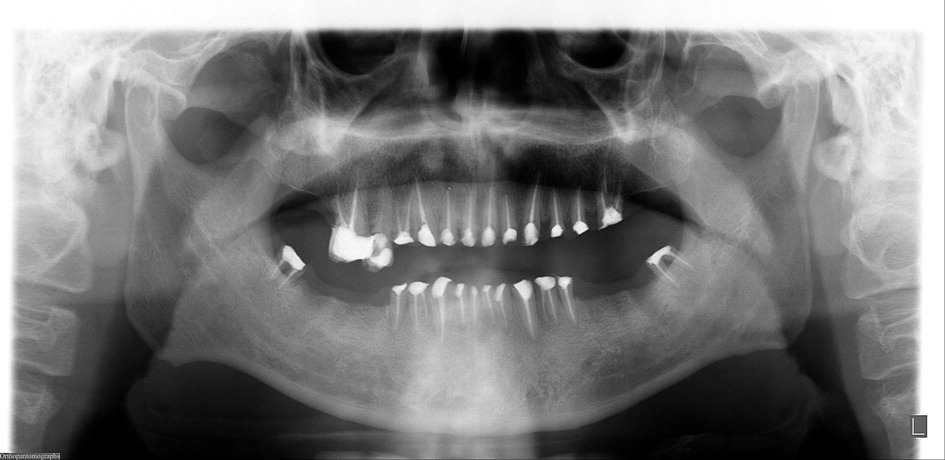

Methamphetamine abuse can affect oral hygiene, causing decay and gum disease. This condition is often referred to as “Meth mouth.”

- The severe tooth decay and gum disease caused by meth abuse can often lead to teeth falling out or breaking off and almost always bad breath

- This extensive tooth decay is likely caused by a combination of factors such as lack of concern over hygiene due to being high, poor nutrition, clenched jaws, grinding teeth, indulging in other activities that are bad for dental hygiene

The severe tooth decay and gum disease caused by meth abuse can often lead to teeth falling out or breaking off and almost always bad breath. An examination of over 550 meth abusers found that:

- 96% had cavities

- 58% had untreated tooth decay

- 31% had six or more missing teeth

Symptoms of meth mouth often include teeth being blackened, stained, rotting, crumbling, and falling apart. In most instances, the affected teeth cannot be salvaged and will result in tooth extractions. This extensive tooth decay is likely caused by a combination of factors such as lack of concern over hygiene due to being high, poor nutrition, clenched jaws, grinding teeth, indulging in other activities that are bad for dental hygiene (smoking cigarettes, sugary beverages, etc.), and other physiological and psychological changes caused by abuse.

In addition to this, methamphetamine is also acidic, meaning those who smoke the substance will directly erode their teeth. The above study also showed that the longer someone abused meth, the more likely they would develop gum disease and tooth decay. For instance, people over 30 years or older who had been using meth for a long time would have more oral issues than someone of the same age who hadn’t, as was the case with smokers.